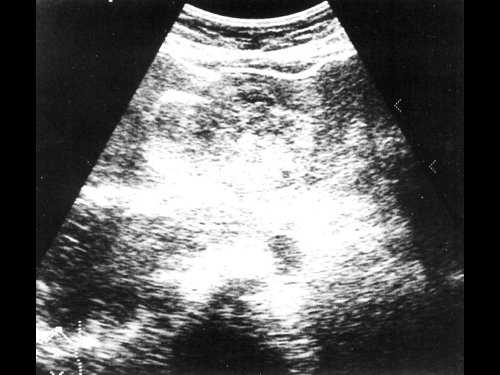

Женщина 50 лет, госпитализирована с болями в верхнем правом квадранте живота. Ультразвуковое исследование органов брюшной полости было проведено в день поступления (рис. 1а, б).

a) На эхограмме в правой доле печени видны два гиперэхогенных образования с четкими контурами (3,0x1,5 см, 2,5x1,5 см).

б) На эхограмме в левой доле печени видно большое гетерогенное образование (5.0x4.0 см), имеющее дольчатое строение.

Диагноз - множественная гемангиома печени